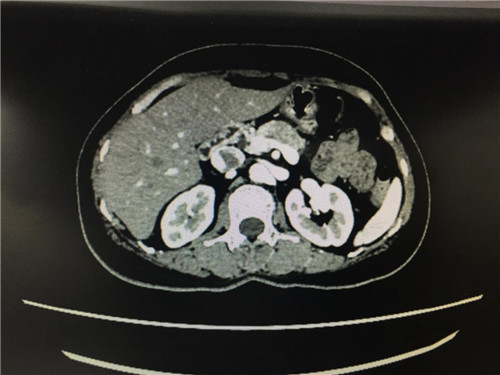

2月12日,普外科收治了一名女性患者,该患者入院一个月前,无明显诱因出现上腹部疼痛不适,呈间断性,向腰背部放射,有恶心,无呕吐,近一个月体重下降了5kg。门诊查上腹部CT提示:胰颈部新生物并胰管扩张;副脾。

患者病情复杂,在潘承恩教授和全科医生的讨论下,结合检验及检查结果,术前胰腺颈体部肿瘤诊断明确,科室积极制定手术方案,详细向家属探明病情并取得合作。2月21日,由普外科史和平主任、梁鹏锋医师主刀,在王谦、李垚磊医师配合下,成功对该患者实施了剖腹探查、全胰腺切除、脾脏切除术。手术中发现,患者胰腺颈体部可触及一大小约4cm包块,胰头部质软,胰腺体尾部质硬,遂决定行胰腺颈体尾部切除及脾脏切除术。在胰腺近侧断端切取部分胰腺组织送术中快速冰冻,提示查见异型增生的胰腺腺泡样组织,联系病理科考虑癌细胞残留,术中向家属谈明病情并取得同意,遂行胰十二指肠切除术,手术顺利,术后生命体征平稳,并于术后第四日进行了复查CT结果良好。